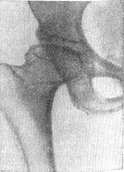

![]() Рис. 3. Хвороба Пертеса, V стадія. Первинно-кістковий деформуючий остеоартроз. |

V. Стадія наслідків перенесеного асептичного некрозу, коли залишаються характерні деформації кульшового суглоба (рис. 3). Через багато років після клінічного одужання і при задовільному стані хворого (залишається лише невелике обмеження ротації і відведення кінцівки у кульшовому суглобі), вже в зрілому віці в суглобі розвивається картина деформуючого остеоартрозу (див.).